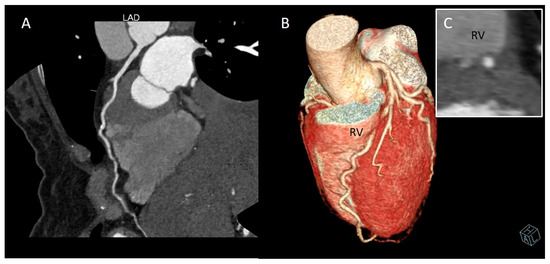

2. CCTA Imaging Protocol

3. Role of CCTA: Anatomical Evaluation